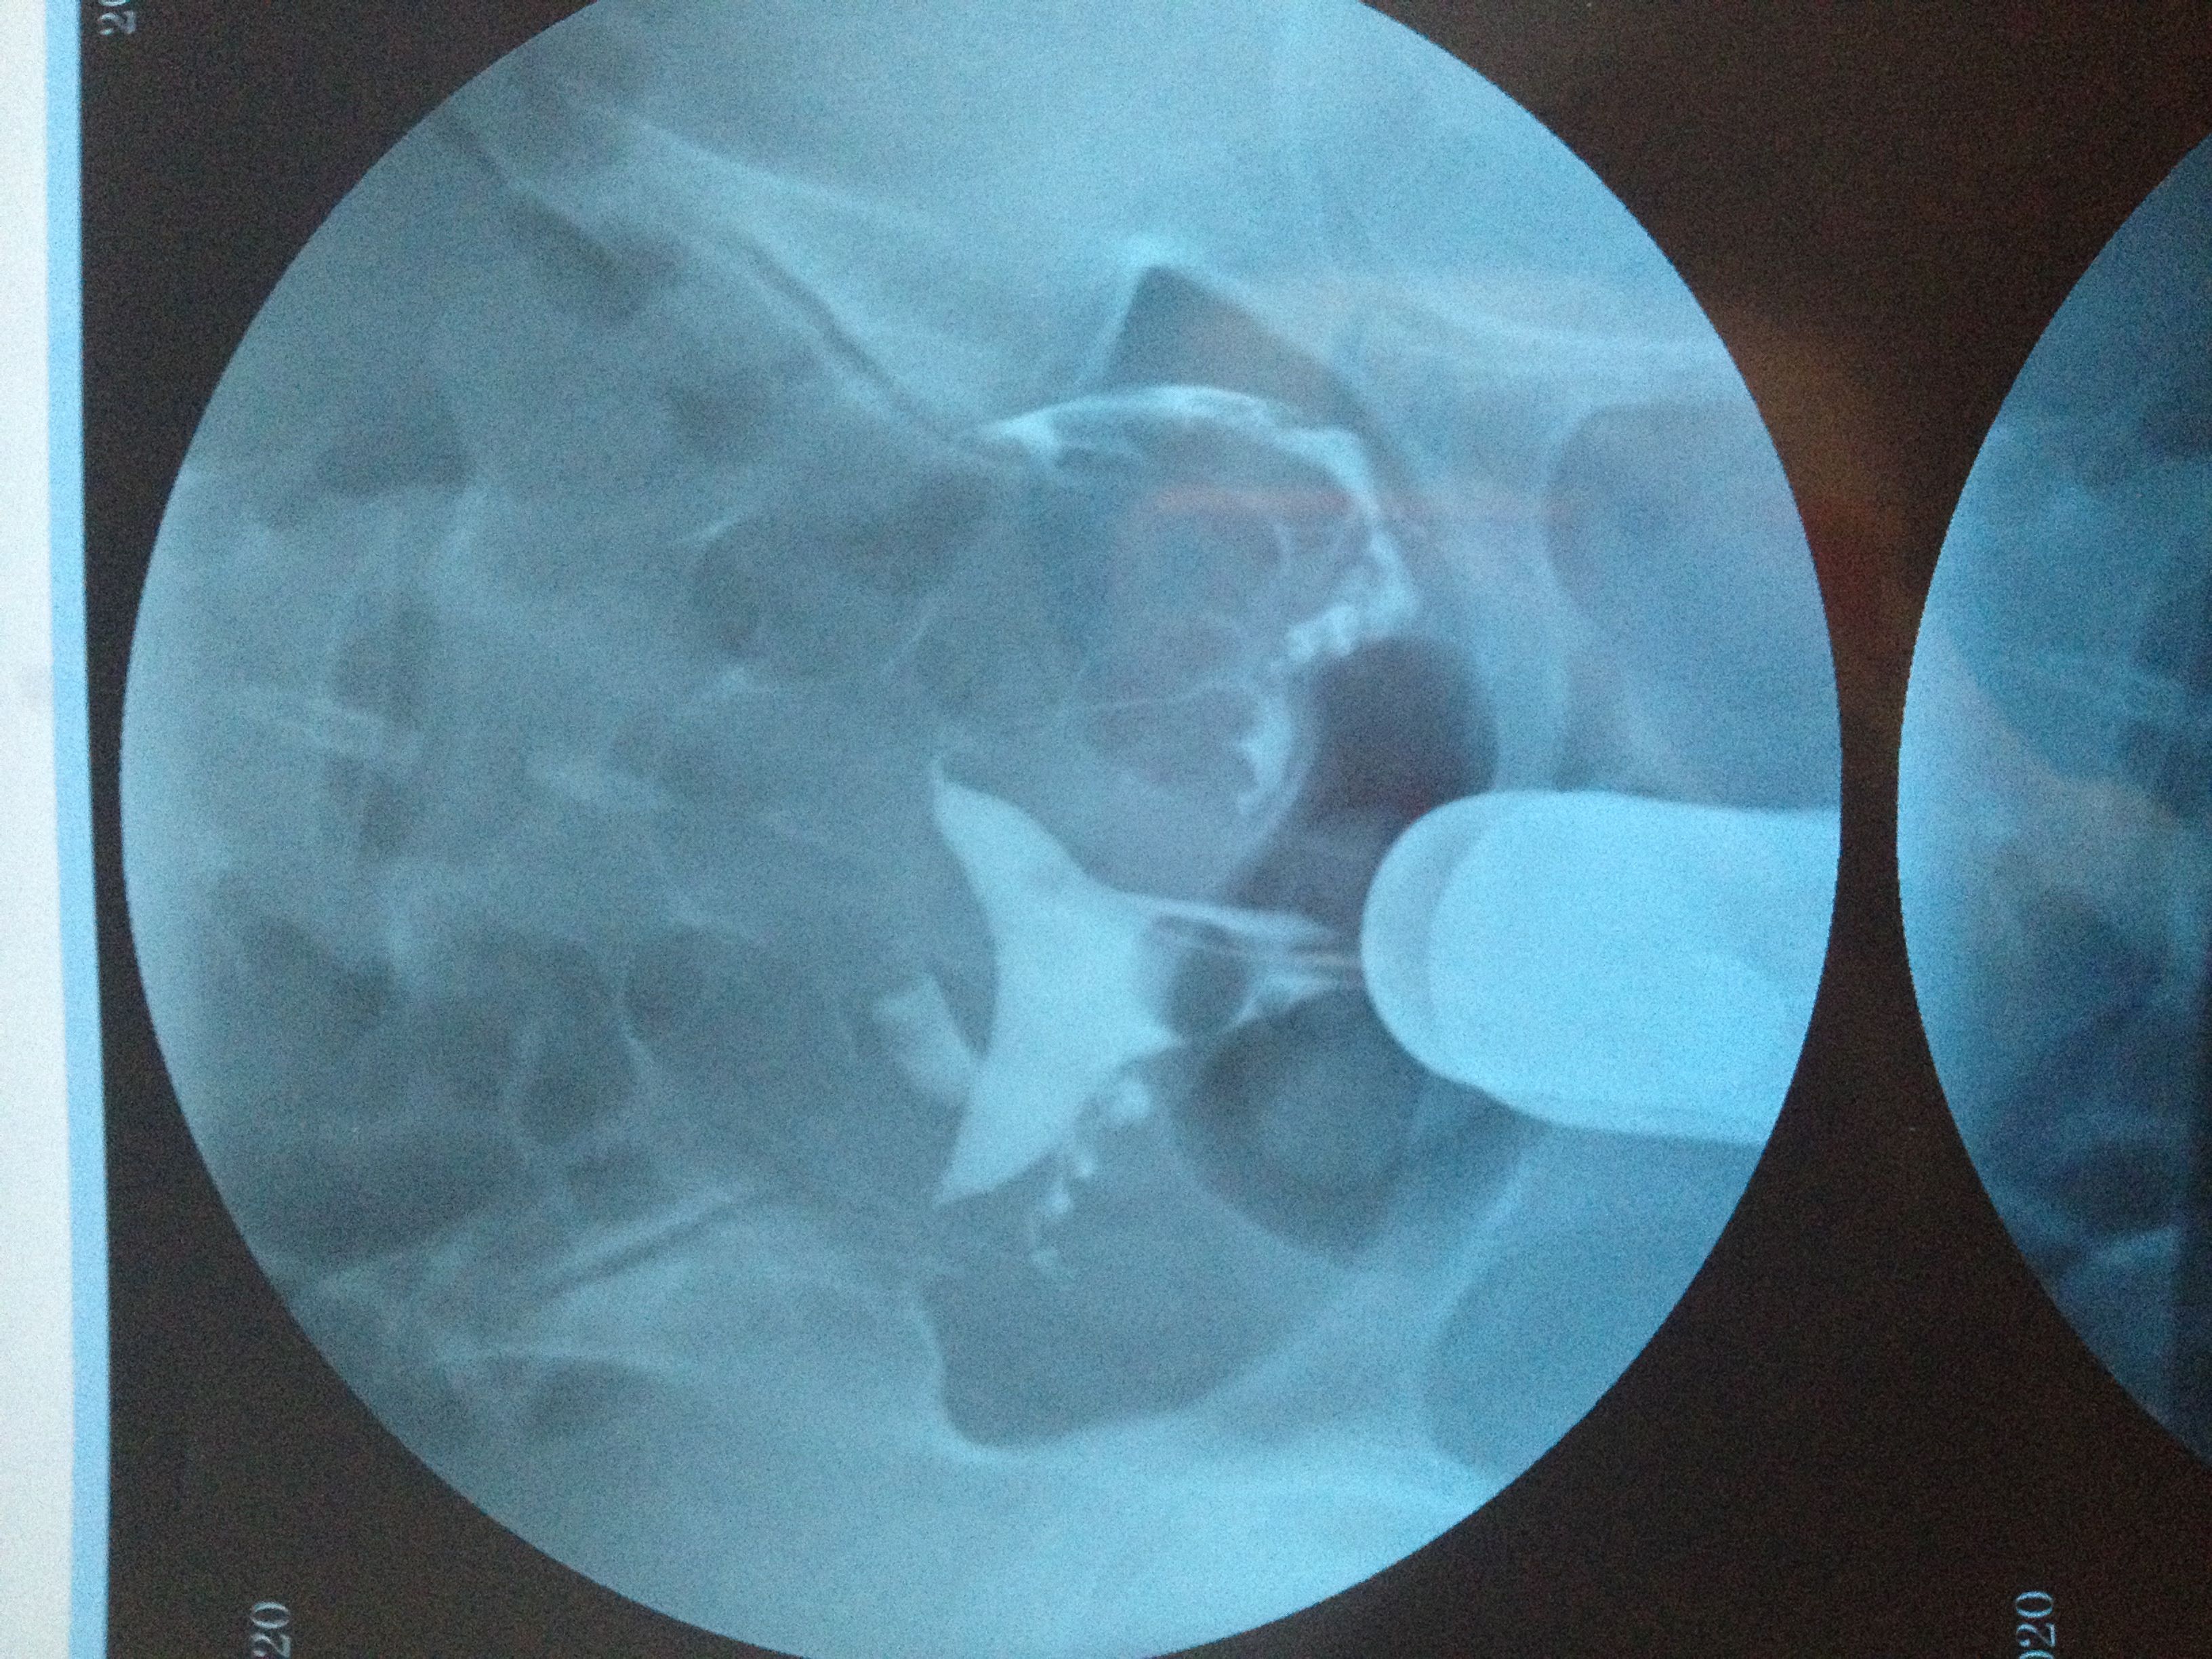

我输卵管照影上写: 子宫呈鞍形 右侧输卵管走形迂曲 下移 有嵌顿 伞端有照影剂聚集与涌出 左侧走

病情分析: 输卵管堵塞的治疗原则是依据堵塞部位的不同采取有效的、合理的治疗方法。 指导意见: 输卵管间质部、峡部堵塞最佳治疗方法是输卵管介入复通术,输卵管壶腹部梗阻没有好的治疗方法,可考虑试管婴儿。输卵管伞端堵塞(积水),可做伞端造口术,有腹腔镜下造口术和开腹造口术。